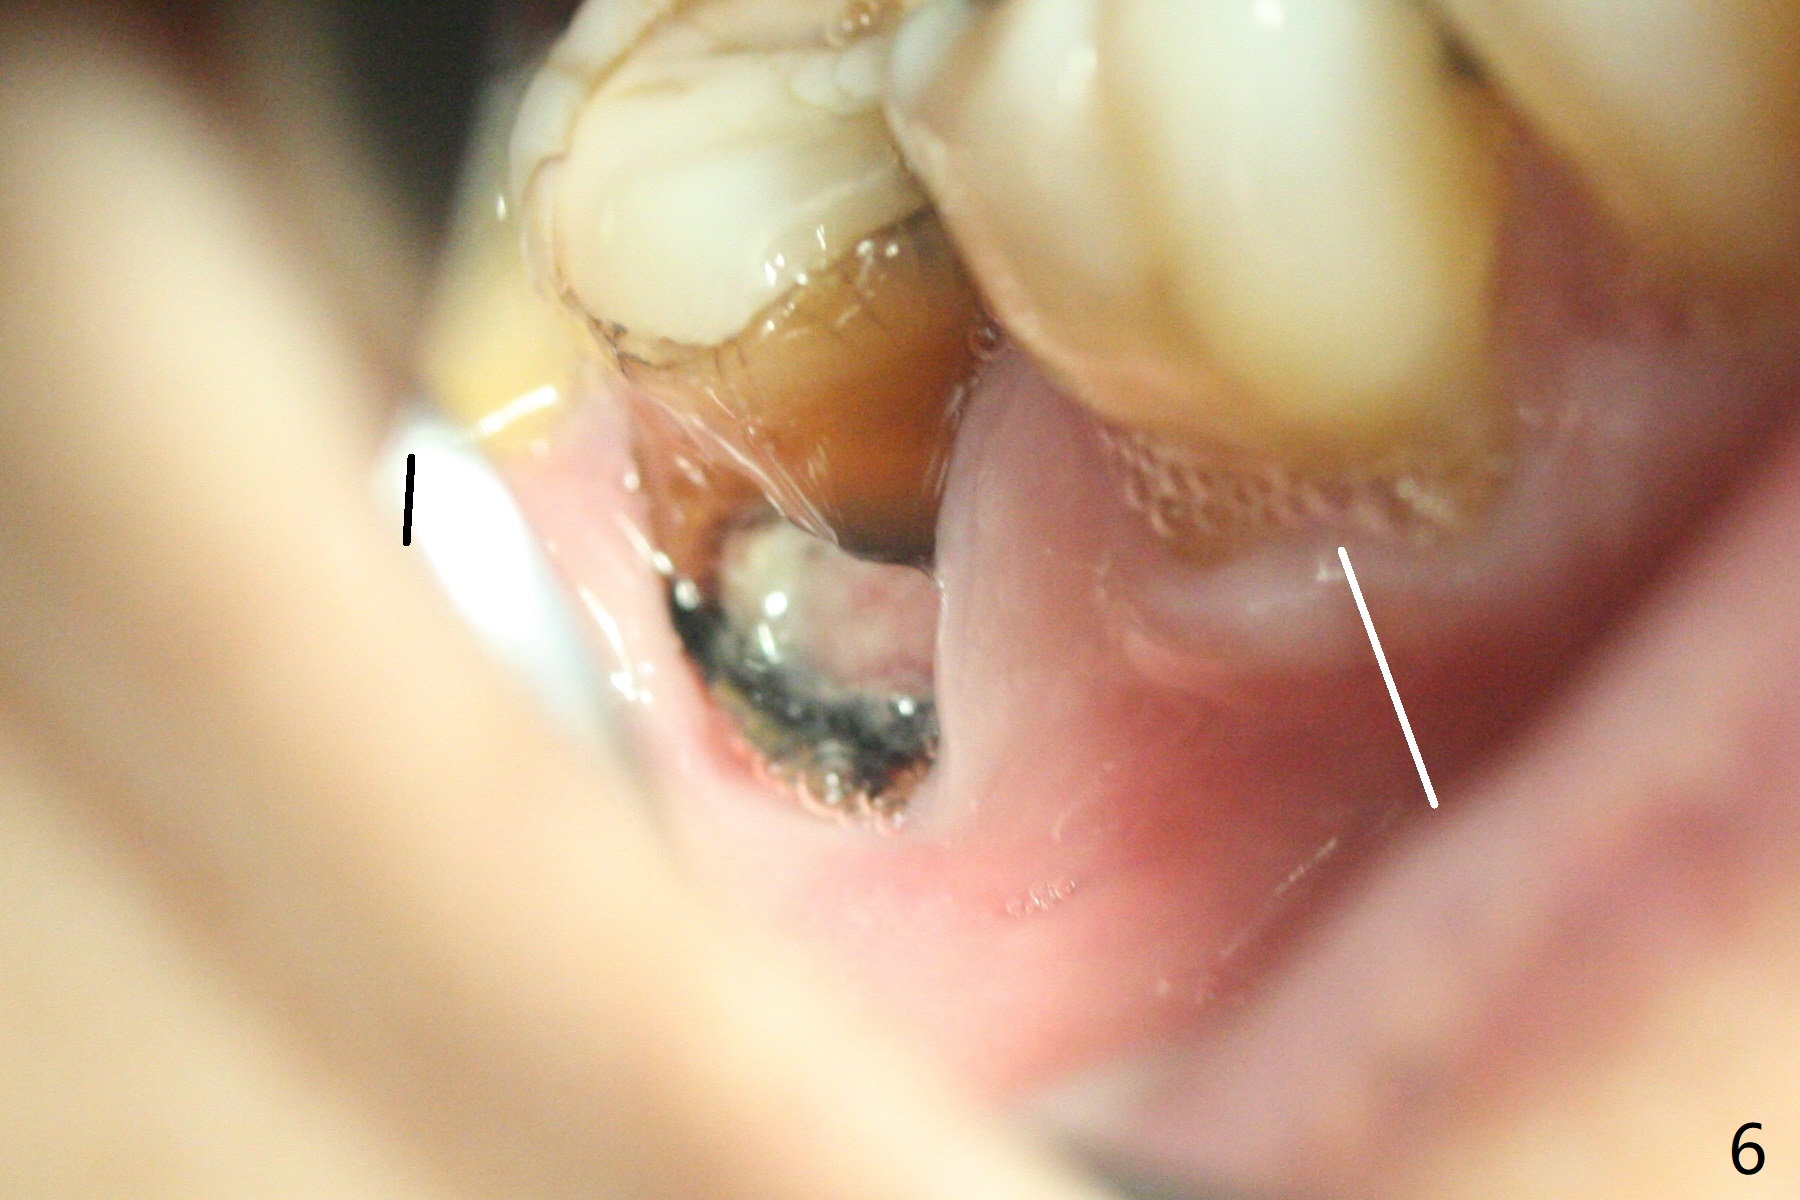

In fact the buccal gingival recession at #31 is asso-ciated with cervical caries perfor-ation (Fig.1 P). The debrided socket is packed with mine-ralized cortical: cance-llous mix (50:50) (better using mine-ralized cortical allograft (future particle size: 125μm – 850μm)) hydrated with ~ .25 ml of .3 mg/ml of rhPDGF-BB (one compo-nent of GEM21S, Fig.2,3). It is extremely difficult to close the socket opening with buccal defect with Osteogen Plug, 12x12 mm BioXclude and 4-0 PGA suture (Fig.4). Acrylic dressing is unstable in spite of several reline (Fig.5 A). Its replace-ment is GEM Cap RCM (regenerative collagen membrane), 9-12 month resorption time, which will be fixed in place with Perio Glue. Watch Video. In fact, 2 pieces of the reline dislodge in the 1st 2 days postop, while the whole piece 3rd days postop. The patient feels better when the acrylic dressing is out. It appears that the bone graft does not fall out, according to phone visit during coronavirus outbreak. A third method to close the buccal defect is to make mesial and distal release incisions (Fig.6) and transfer the flaps (Fig.7). In fact the bone graft gets lost, revealed over phone. Immediate implant is the most secure method to keep the bone graft. PRF may be more retentive. The fourth way is to place Cytoplast, which is fixed with spacer and periodontal dressing.